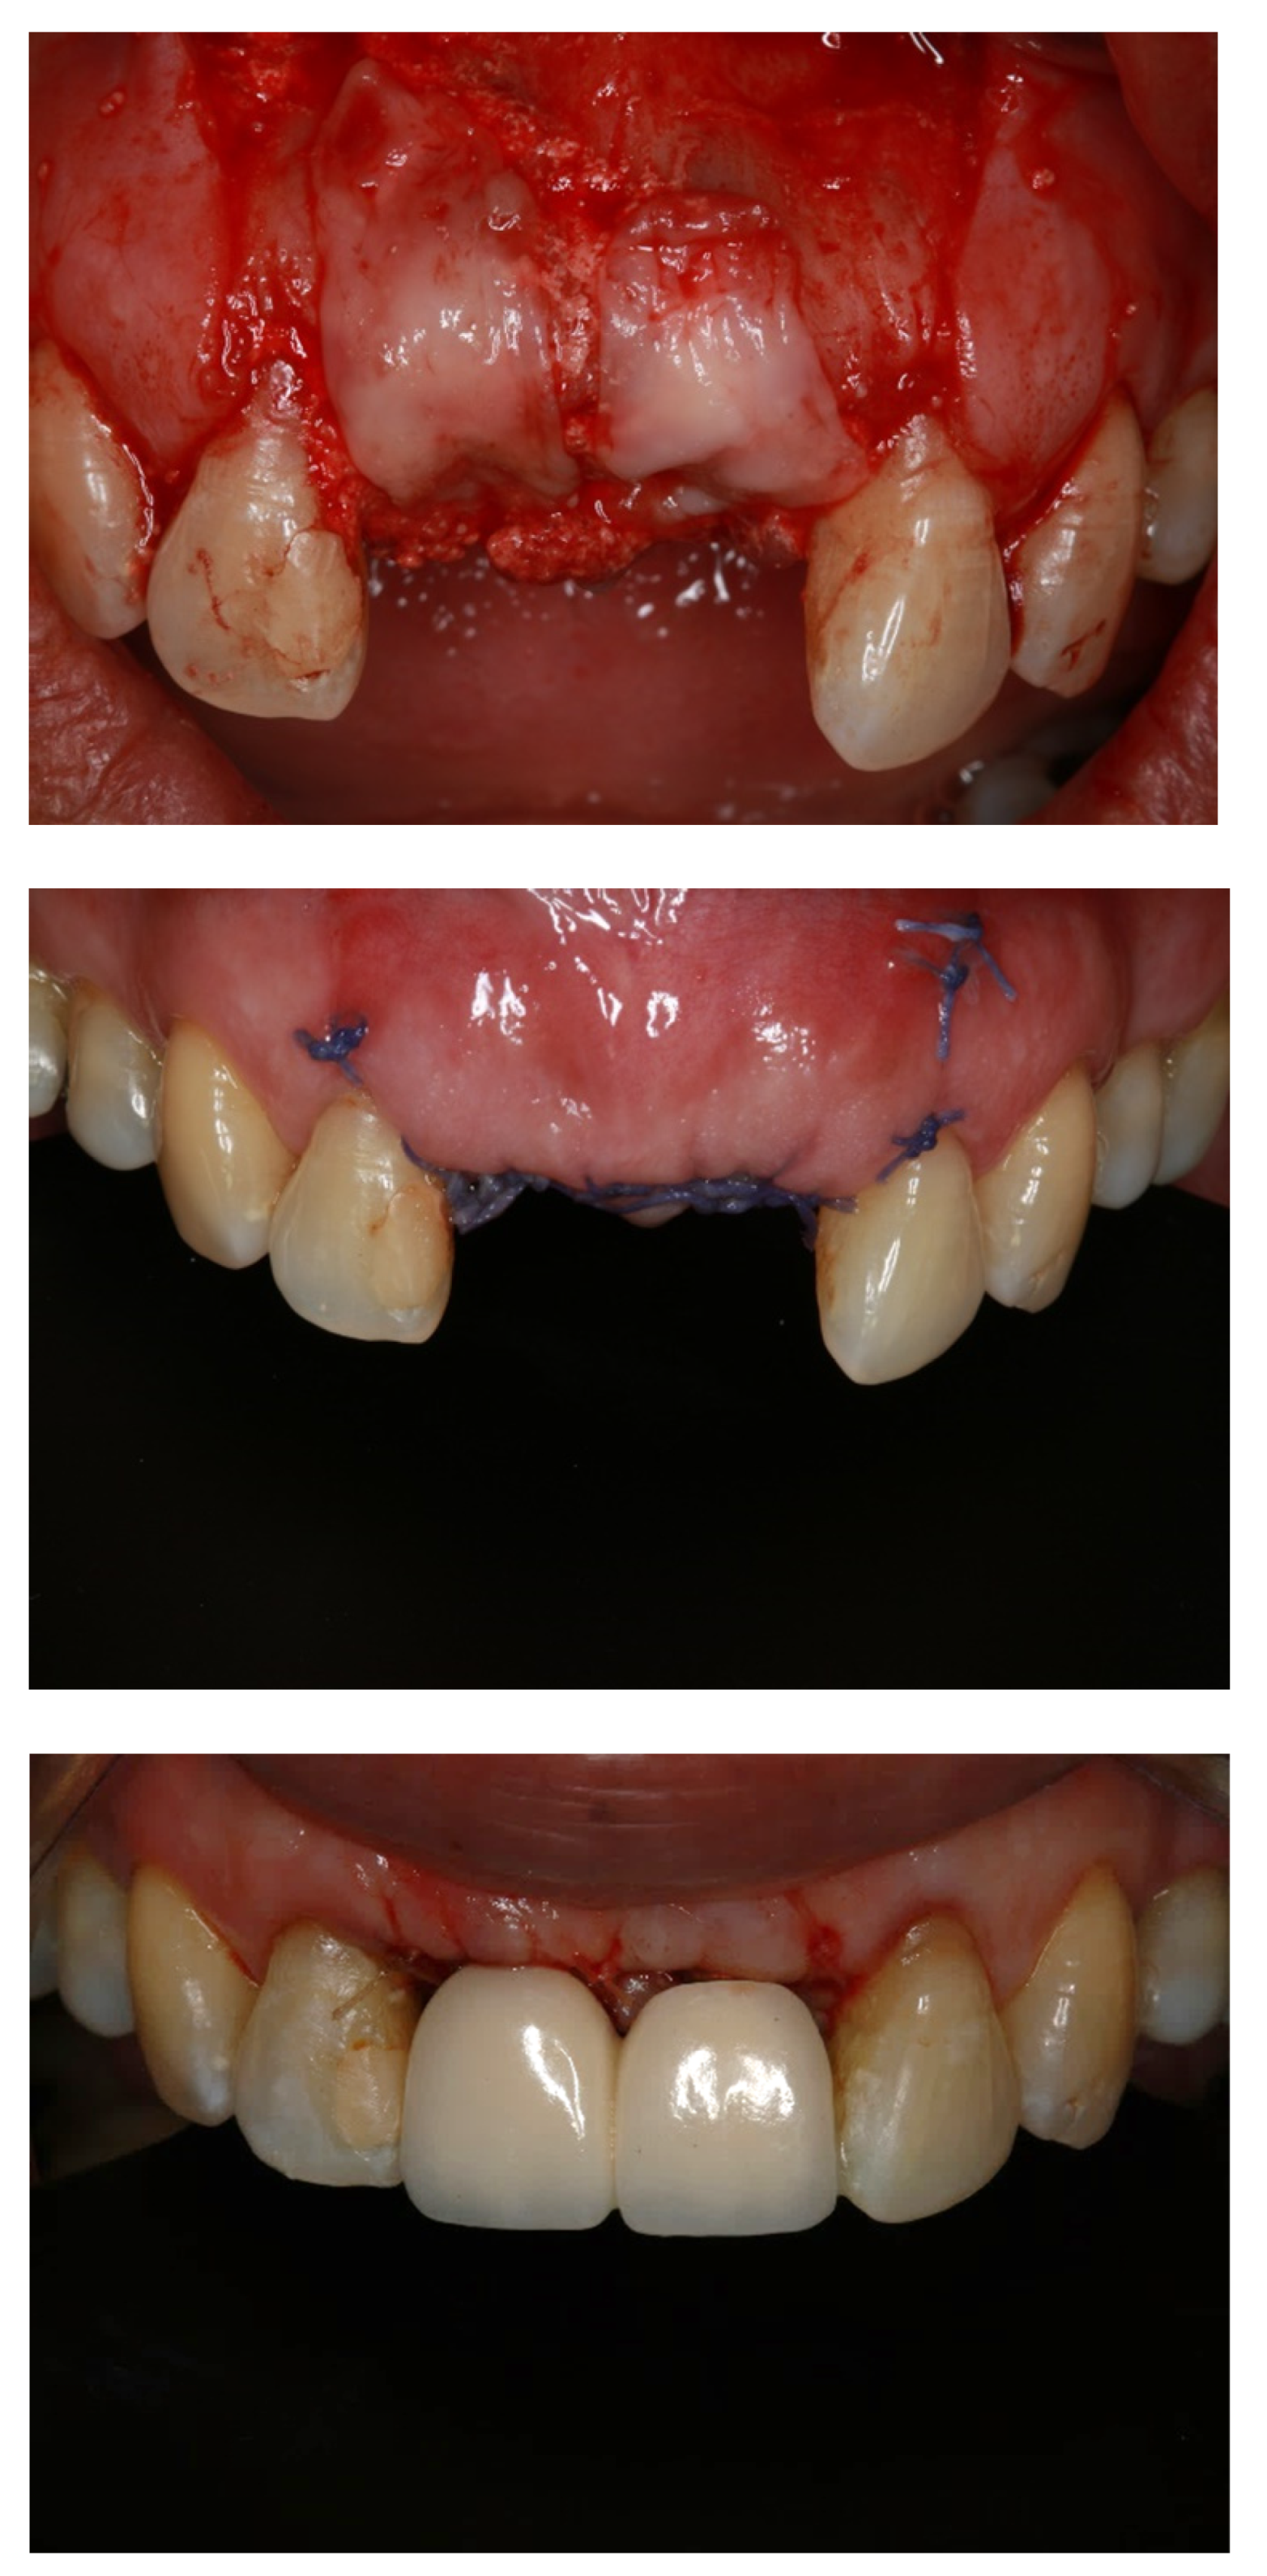

- Alauddin, M.S.; Ramli, H. Management of Membrane Exposure Utilizing Concentrated Growth Factor (CFG) in Guided Bone Regeneration: A Clinical Report. Open Dent. J. 2020, 14, 763–768. [Google Scholar] [CrossRef]